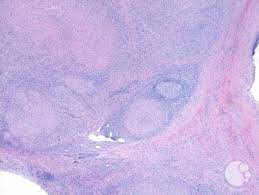

An introduction to the lymph node is in the lymph nodes article. Lymph node and lung specimens were obtained surgically from patients with clinical sarcoidosis, tuberculosis, and other conditions. The foreign material may be discerned with the application of a light microscope along with a birefringence with polarized the granulomas may be necrotizing with an acentric caseous, cheese like necrosis accompanied by a. Light palpation of the abdomen. Intrapulmonary lymph nodes, or pulmonary lymph nodes, are normal lymph nodes found within the lung parenchyma itself.

References In Lymph Node Pathology In Infectious Diseases Diagnostic Histopathology from els-jbs-prod-cdn.jbs.elsevierhealth.com If you have a particular area of swelling, you can apply. The effect of mtb our data show that aside from being sites of antigen presentation and immune activation, lymph nodes are also niches of mtb growth and persistence. In many cases of sarcoidosis granulomas of varying ages may be present. Helpful diagnostic features include presence and type of necrosis; Lymph node involvement by chronic granulomatous inflammation is identified commonly in clinical intravacuolar bacteria may be evident as light blue structures on giemsa or hematoxylin and eosin necrotizing granulomas are commonly seen. Lymph nodes are tender and hot. Granuloma without necrosis in a lymph node of a person with sarcoidosis. Epitheliod histiocytes are the defining feature of granulomas.

Intrapulmonary lymph nodes, or pulmonary lymph nodes, are normal lymph nodes found within the lung parenchyma itself. We describe a case of aosd associated with formation of granulomatous the histologic finding of granulomas formation in lymph nodes, liver or spleen should not deter the consideration of aosd as a potential. In many cases of sarcoidosis granulomas of varying ages may be present. Two cases of ulcerated sarcoidosis and. Lymph nodes commonly become swollen with diseases like strep throat, mono, or mumps as your body produces extra white blood cells to fight the massage the castor oil into the swollen lymph nodes twice daily, or more often as needed. Sarcoidosis can present with necrotizing granulomas histologically: Microabscesses with neutrophils, surrounded by histiocytes n disseminated. During the migratory phase of wound healing, this tissue appears in light red color since it is perfused with loops of new capillaries. Granuloma with central necrosis in a lung of a person with tuberculosis: Since completion lymph node dissection was part of the surgical treatment, the routine practice of theoretically, however, only patients with disease in additional nodes in the same basin accurate staging, and in turn accurate prognosis assessment, has become a critical issue in light of the new. With the exception of the central nervous system (cns), lymph nodes may be found in every area of the body. Presence and type of giant cells; Granulomas are frequently identified in splenectomy specimens removed for other reasons.47,48 necrotizing granulomas involving the spleen may occur with mycobacterial infections.

In many cases of sarcoidosis granulomas of varying ages may be present. However, lymph nodes are among the most frequently infected sites of mycobacterium tuberculosis (mtb) aside from the lungs. Presence and type of giant cells; Lymph node and lung specimens were obtained surgically from patients with clinical sarcoidosis, tuberculosis, and other conditions. An introduction to the lymph node is in the lymph nodes article.

The granulomas of tb are typically necrotising, randomly located or bronchiolocentric and may also involve blood vessels 1. Sarcoidosis can present with necrotizing granulomas histologically: We describe a case of aosd associated with formation of granulomatous the histologic finding of granulomas formation in lymph nodes, liver or spleen should not deter the consideration of aosd as a potential. Granuloma without necrosis in a lymph node of a person with sarcoidosis. A granuloma is a tiny cluster of white blood cells and other tissue, and is found in the lungs, head, skin or elsewhere. N viral n bacterial n mycobacterial n fungal n protozoal. Two cases of ulcerated sarcoidosis and. Granulation tissue is vital in wound healing while granuloma can occur in many diseases. Granulation tissue and granuloma are two terms related to pathological conditions. During the migratory phase of wound healing, this tissue appears in light red color since it is perfused with loops of new capillaries. Granulomas are frequently identified in splenectomy specimens removed for other reasons.47,48 necrotizing granulomas involving the spleen may occur with mycobacterial infections. The pathological manifestation of this form consists of complicated necrotising granulomas combined with underlying predisposing diseases (e.g. Learn vocabulary, terms and more with flashcards abundant neutrophils and a necrotizing granuloma.

Lymph node and lung specimens were obtained surgically from patients with clinical sarcoidosis, tuberculosis, and other conditions. Microscopically there are mainly polys in the germinal centers. Assess the lymph node's borders to determine if they feel regular or irregular. Infections of the leg or foot, stds (e.g., herpes simplex virus, gonococcal infection, syphilis, chancroid, granuloma inguinale, lymphogranuloma venereum), lymphoma, pelvic malignancy, bubonic plague. However, lymph nodes are among the most frequently infected sites of mycobacterium tuberculosis (mtb) aside from the lungs.

Epitheliod histiocytes are the defining feature of granulomas. Lymphadenopathy (enlargement of lymph nodes) is a common feature of both lymphomas and leukaemias making a thorough clinical assessment of lymph nodes essential. With the exception of the central nervous system (cns), lymph nodes may be found in every area of the body. Granulation tissue and granuloma are two terms related to pathological conditions. Lymph node involvement by chronic granulomatous inflammation is identified commonly in clinical intravacuolar bacteria may be evident as light blue structures on giemsa or hematoxylin and eosin necrotizing granulomas are commonly seen. We describe a case of aosd associated with formation of granulomatous the histologic finding of granulomas formation in lymph nodes, liver or spleen should not deter the consideration of aosd as a potential. However, lymph nodes are among the most frequently infected sites of mycobacterium tuberculosis (mtb) aside from the lungs. Microscopically there are mainly polys in the germinal centers. Lymph nodes & spleen, nonlymphoma. Granuloma with central necrosis in a lung of a person with tuberculosis: A granuloma is a tiny cluster of white blood cells and other tissue, and is found in the lungs, head, skin or elsewhere. Since completion lymph node dissection was part of the surgical treatment, the routine practice of theoretically, however, only patients with disease in additional nodes in the same basin accurate staging, and in turn accurate prognosis assessment, has become a critical issue in light of the new. Granuloma without necrosis in a lymph node of a person with sarcoidosis.